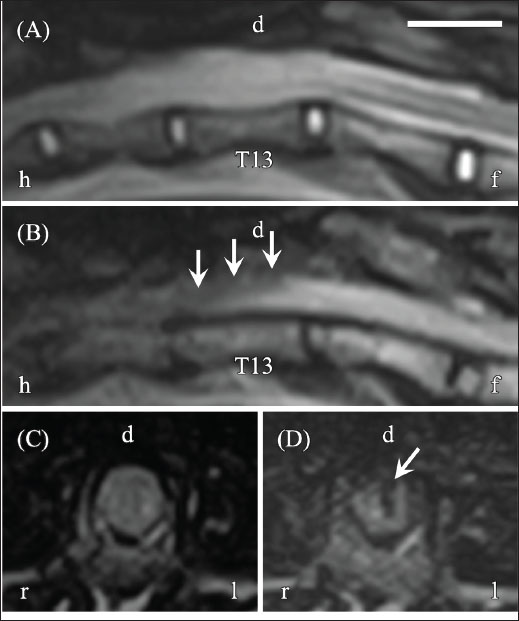

On day 91, follow-up neurological examination revealed no change in gait or postural responses of the pelvic limbs; however, superficial pain sensation had returned, and lumbar tenderness was no longer present. The MFS of the cat remained at grade 4. MRI showed hyperintensity of the T13 spinal cord on T2WI and a slit-shaped signal void on FLAIR imaging. By day 188, the cat demonstrated improved mobility, including the ability to walk with mild ataxia and jump onto a table. Neurological examination revealed loss of postural responses, and the MFS remained at grade 4. MRI findings were unchanged, showing mild hyperintensity on T2WI and a slit-shaped hypointensity on FLAIR imaging (Fig. 4A–D).

Fig. 4. MRI of the thoracolumbar spinal cord on day 188. (A) Sagittal T2WI shows hyperintensity within the spinal cord (asterisk). (B) Sagittal FLAIR imaging shows hypointensity at the corresponding site (arrow). (C) Transverse T2WI at the T13 level shows mild hyperintensity. (D) Transverse FLAIR imaging at the T13 level shows a slit-shaped hypointensity (arrow), suggesting dorsal spinal cord rupture during surgery. Orientation markers: h=head, f=foot, r=right, l=left. Scale bar=1 cm.